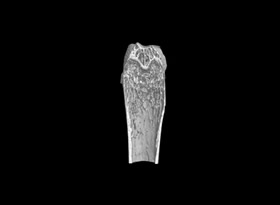

用于骨質疏松和關節(jié)炎動物模型潛伏期的骨結構和密度改變的研究。MicroCT是目前研究骨立體結構、容量和微結構細微改變較好方法。

1骨組織樣本掃描。

2提供2D圖、3D圖和相關參數(shù)的分析數(shù)據(jù)(骨密度BMD 單獨收費)。